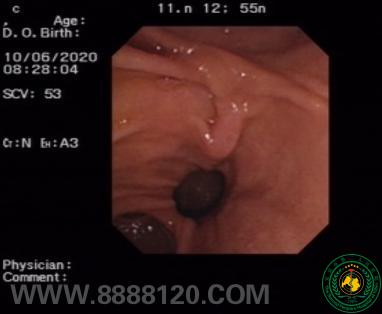

①十二指肠镜探查肠腔,见十二指肠乳头旁憩室,增加插管难度28189